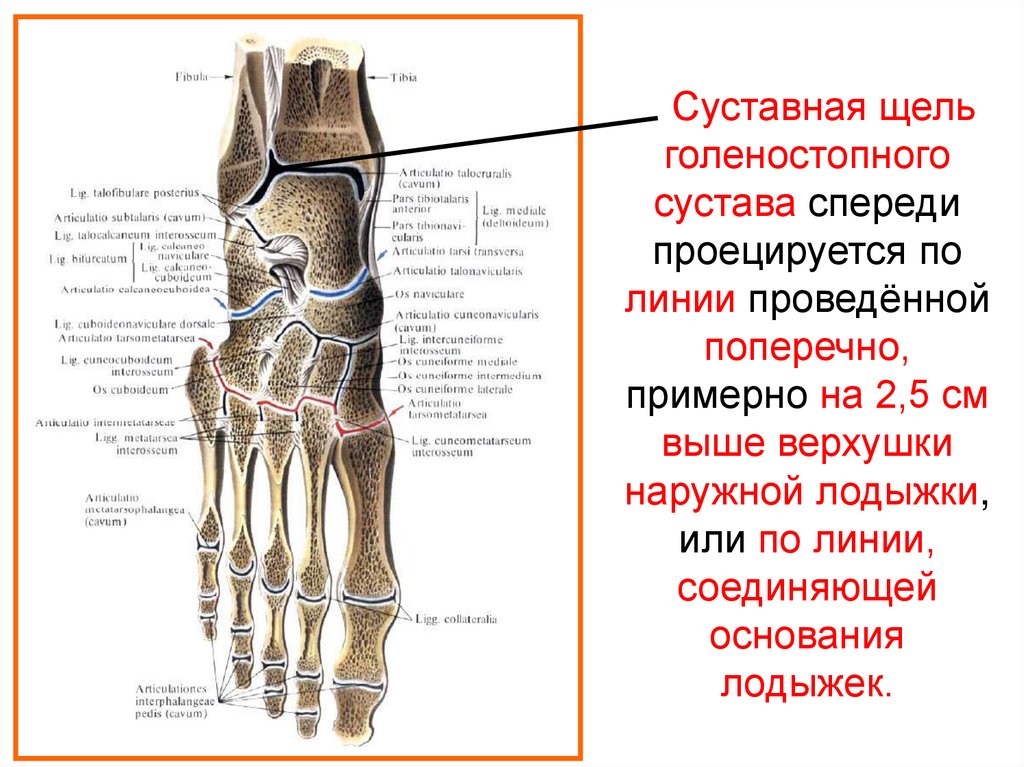

Анатомия суставов Шапарова и Лисфранка: фото и информация